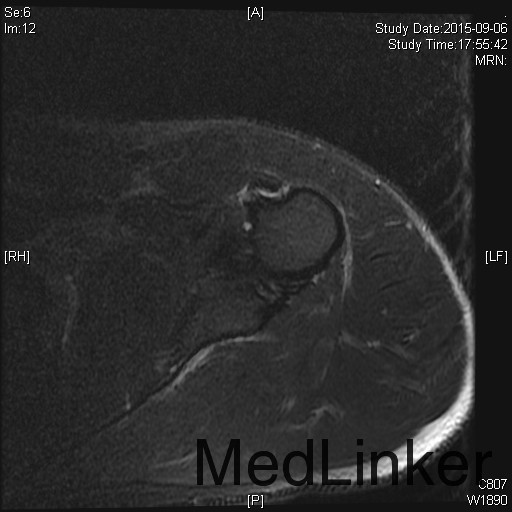

主诉:左肩扭伤后疼痛不适伴弹响10余年,加重3月。 现病史:患者10余年前扭伤左肩关节后出现疼痛不适等症状,伴活动时弹响,以运动时明显。患者当时未重视,未就诊。10余年来患者左肩疼痛不适症状反复发作,曾至外院行局部理疗、小针刀等保守治疗,效果不佳。3月前患者再次扭伤左肩,当即感觉左肩症状加重。来我院就诊,我院行MRI检查示:左肩盂唇信号异常及肱二头肌长头肌腱信号异常。

1、诊断:左肩创伤性前不稳定,左肩SLAP损伤。 2、治疗:全麻下行左肩关节镜下前盂唇、上盂唇修补术。